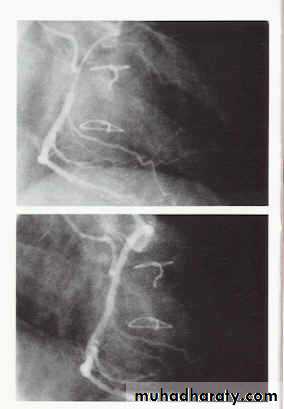

Cause vasodilation due to relaxation of smooth musclesPotent dilating effect on coronary arteries

Used for prophylaxis and treatment of angina